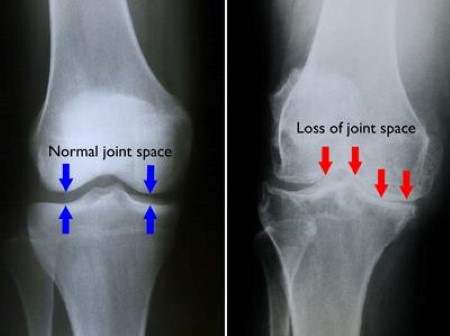

Not all knee pain is arthritis. Learn the key differences between knee arthritis, tendon pain, and meniscus injuries—and when a proper knee pain evaluation in Evansville matters. ...more

Knee pain with aging is often caused by tissue degeneration, reduced load tolerance, and cartilage stress—not just arthritis. Learn what changes over time and how non-surgical care can help. ...more